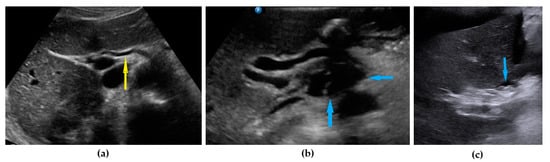

| Ascites | Fluid outside the pouch of Douglas, recorded as being present or absent 1 | Figure 5 | Video S5 |

| Liver, parenchymal lesions | Single or multiple focal parenchymal lesions (with a “halo“ sign, necrosis, and indistinct borders) in the liver. | Figure 6 | Video S6 |

| Liver hilum | Presence of nodules or rigid structures in the region of the hepatic hilum. | Figure 7 | Video S7 |